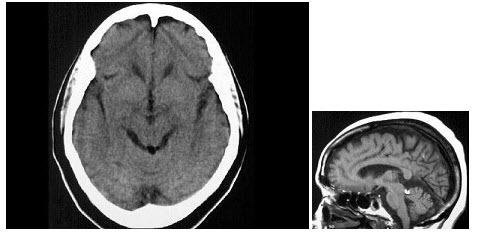

男,45岁,无不适,CT、MRI检查如图,最可能的诊断是()

A.四叠体池脂肪瘤

B.正常颅脑

C.四叠体池囊肿

D.四叠体池积气

E.四叠体池内结核性肉芽肿